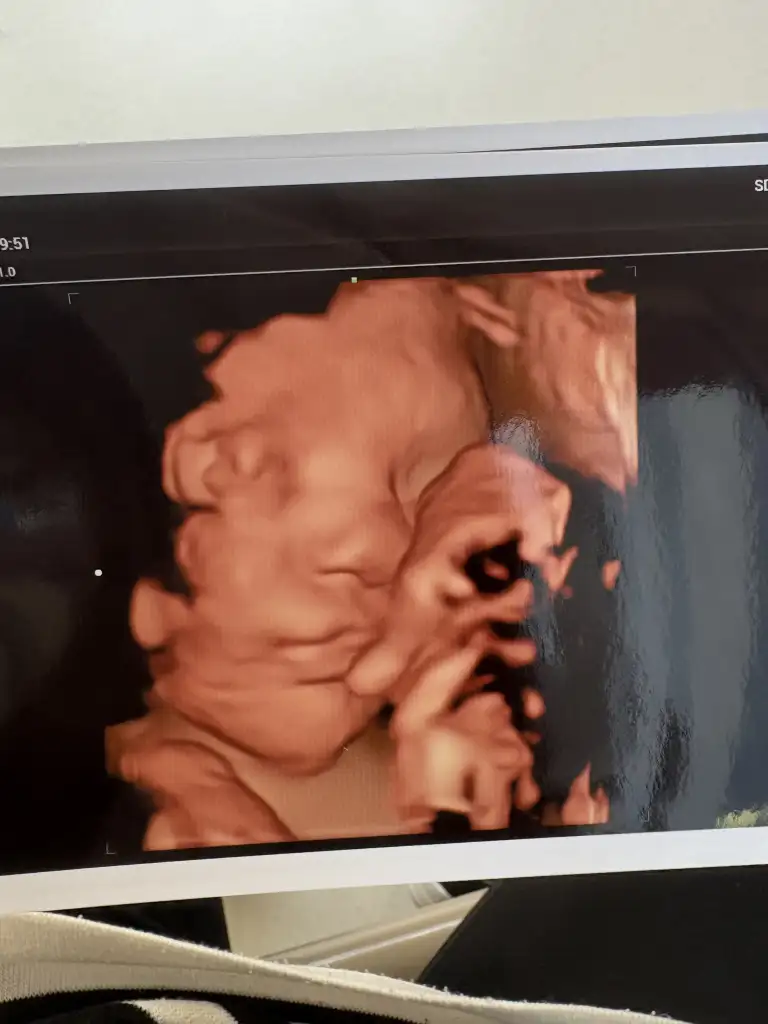

Maşallah güzelliğe, burnunu yesinlerEveett biz geldik ilk nstmize girdik 10 dk kalp atışı ardık bi korkuttu kızım beni

Ye teyzesiMaşallah güzelliğe, burnunu yesinlergülüyor sanki

Zor olsun ama olsunYe teyzesiSomurtuk duruyodu aslında bi anlık gülümseyince çekti doktor hemen burnu babasına benzesin ya benimki estetik